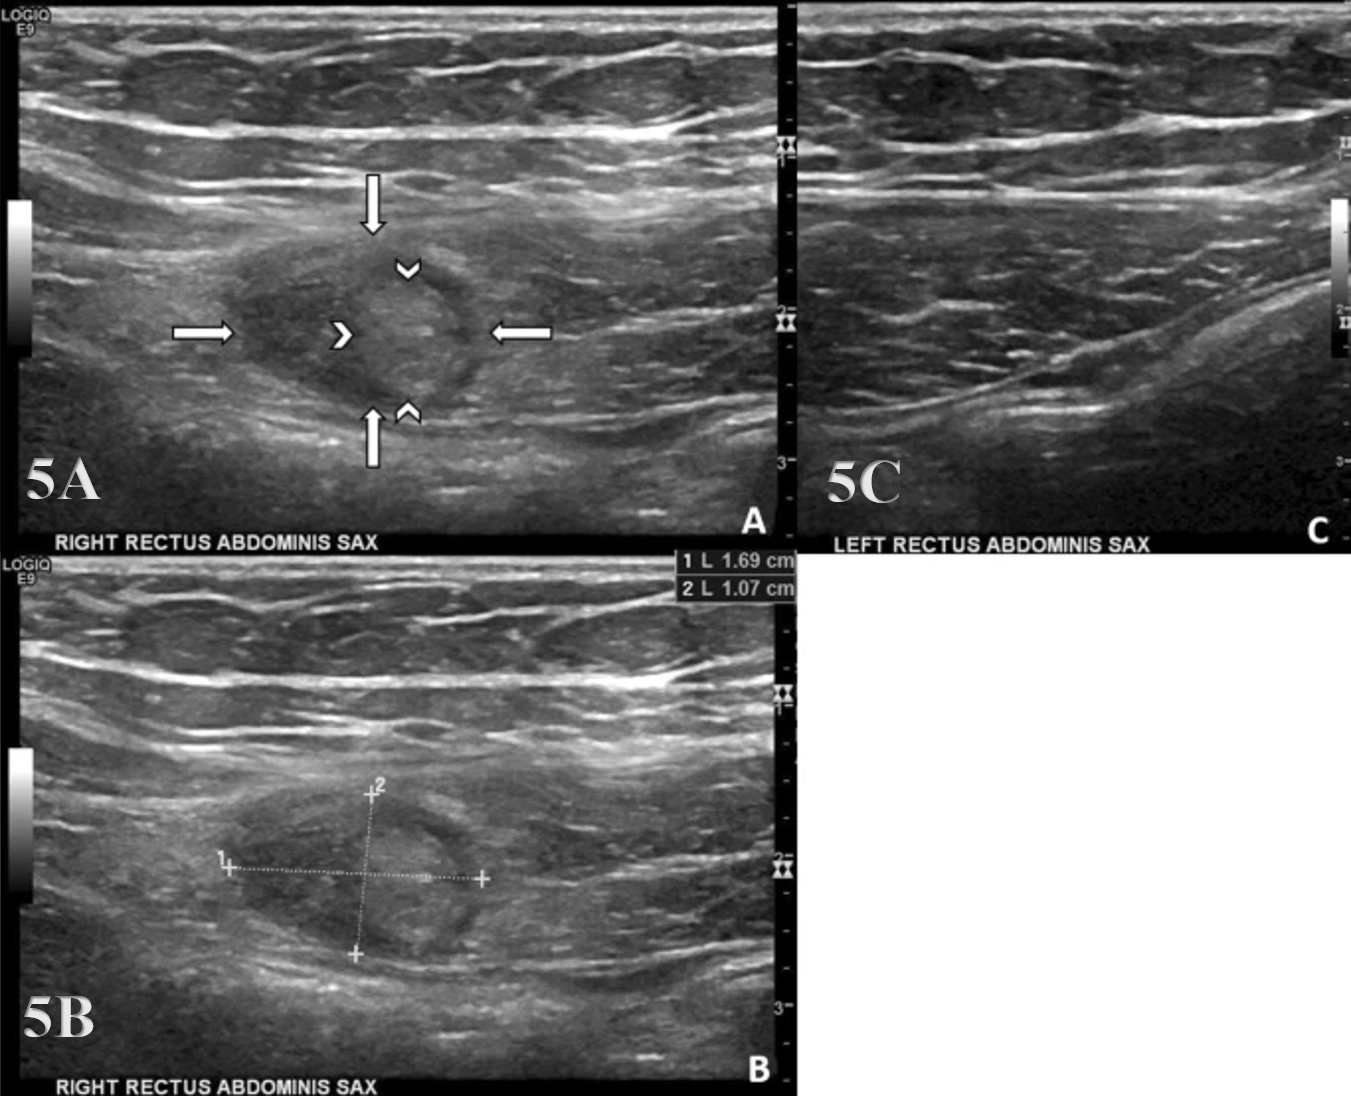

Typically, the transducer will be placed near the proximal portion of the RA perpendicular to the muscle fibers in the SAX. In this position, the transducer can be moved both proximally and distally and can examine the RA in the transverse plane. The cross-section of the RA will be seen as fibular hypoechoic muscle tissue. Additionally, the examiner should be able to easily discern the hyperechoic linea alba and rectus sheath.

Pathologic Findings in Rectus Abdominus Injury

Intramuscular hypoechoic muscle tissue

Disruption of fibrillar pattern in partial tears and ruptures.

Associated hematoma.

Early Detection of Injury / Accurate Injury Grading: MSKUS can quickly differentiate between a strain and a more severe rupture to help guide treatment planning.